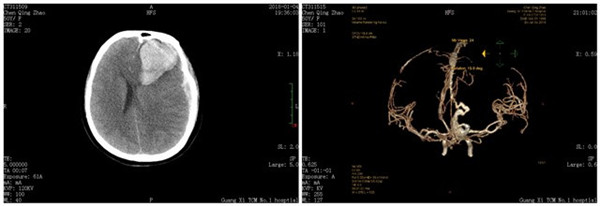

患者陈某某,女性,49岁,四川人,因“突发昏迷2小时”入院,心率一度低至30余次/分,经仙葫院区急诊科团队及时、正确、有效的抢救后,于1月5日晚20:30时转入仙葫院区颅脑外科。既往无高血压病史。入院查体:T 36.2°C,P 52次/分,R 15次/分,BP 185/120mmHg,神志处于深昏迷状态,左侧瞳孔6mm,对光反射消失。放射科急诊行头部CTA检查后进一步明确出血原因,明确诊断:左侧额叶硬脑膜动静脉畸形破裂出血并脑疝形成;患者病情危重,手术难度大、风险高,经全科讨论并及时与家属沟通后,决定急诊行开颅畸形血管团切除术、颅内血肿清除术、去骨瓣减压术及气管切开术。

术前影像